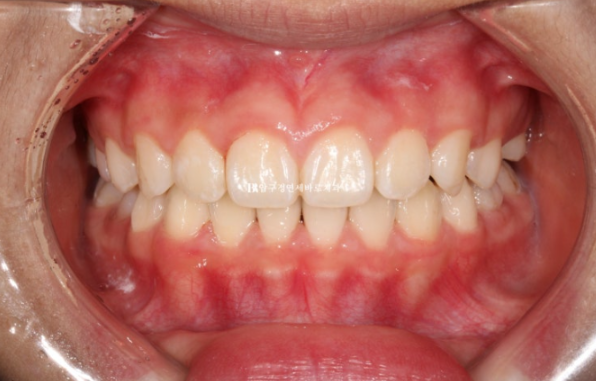

24.09

재제작 총 2번 했고 토탈치료기간은 2년 중간에 쉬는 시간은 5개월 이었습니다.

치료 종료 시점 유치는 2개가 남아있었고 공간이 충분하여 아직 나오지 않은 계승영구치도 예쁘게 내려올 것으로 예상이 됩니다.

악궁확장으로 넓어진 악궁, 그리고 가지런해진 앞니가 눈에 띕니다.

22.08~24.09

중심선도 정확히 맞고 과개교합도 해소가 되었습니다